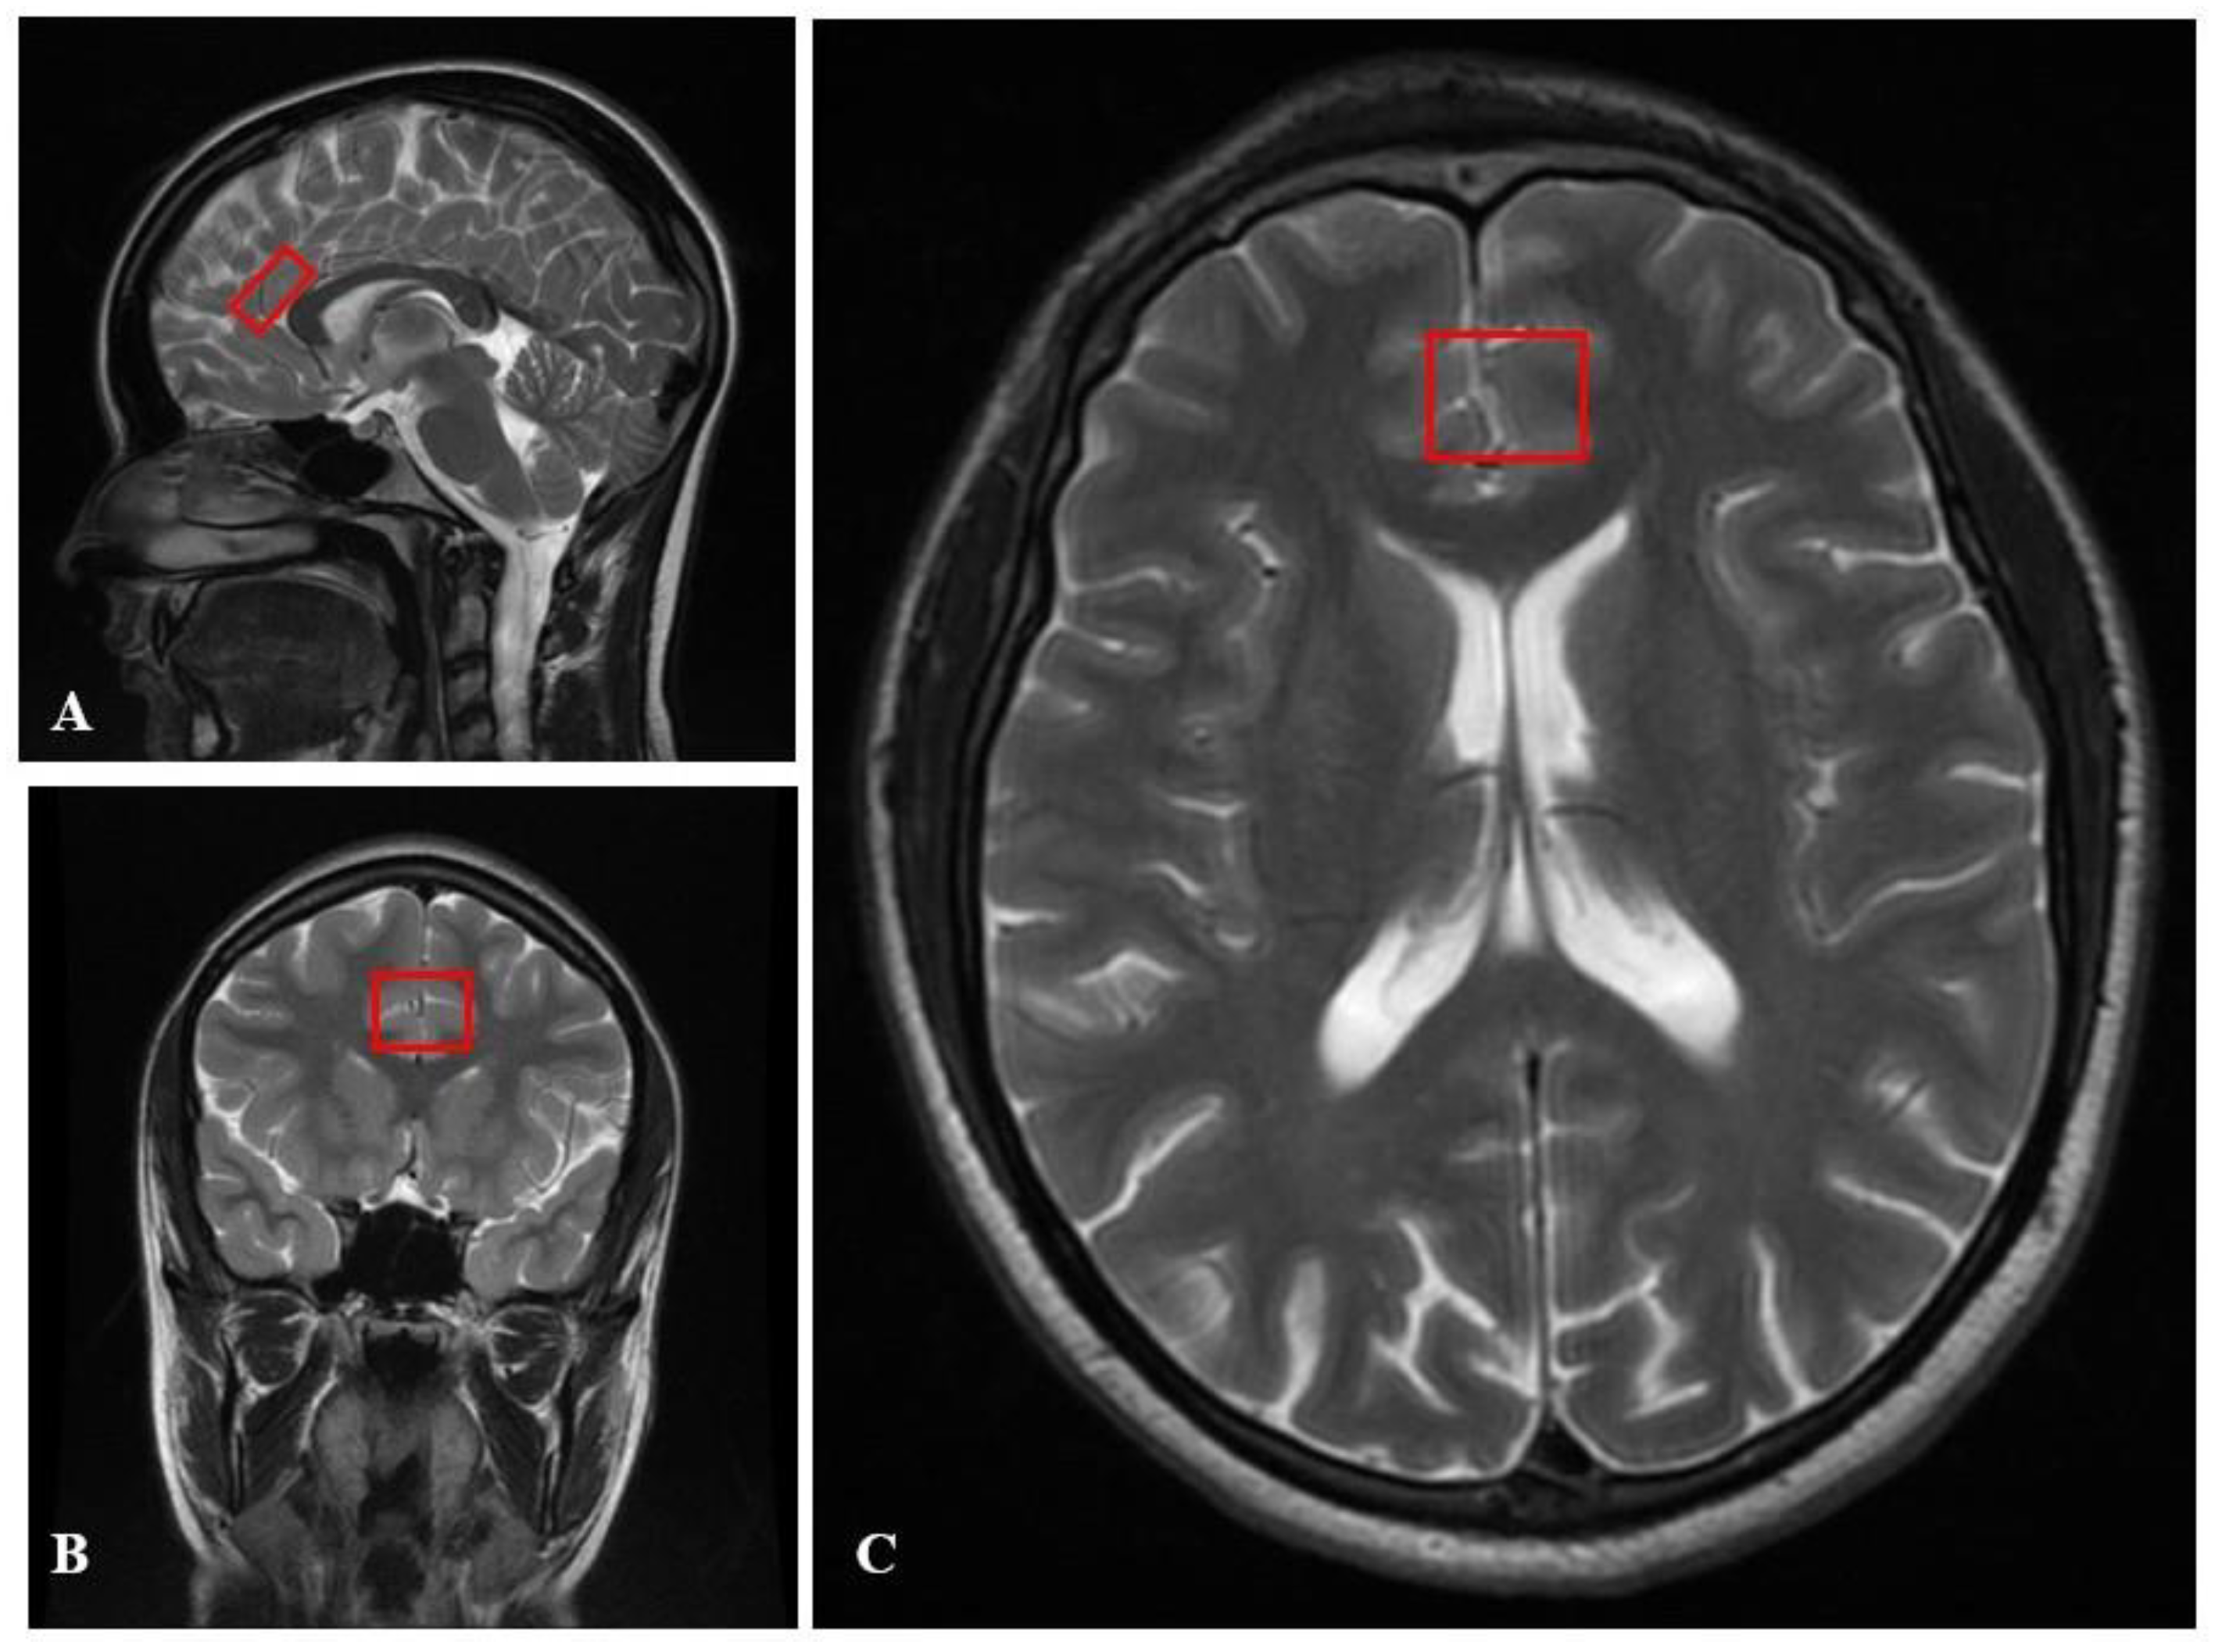

4.6. Neuroimaging Analysis